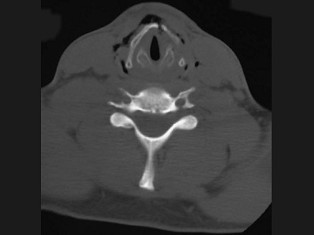

11.27歲男性,開車外出在高速行駛時翻車,呼吸困難,喉部腫脹,CT檢查如圖所示,請選擇正確的描述或診斷  (    )

正確答案:ABCE